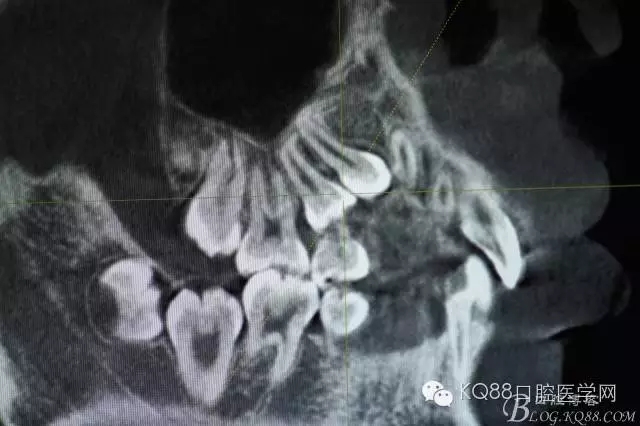

圖4.從局部影像,可以看出14牙冠位于15牙冠與13牙根之間。